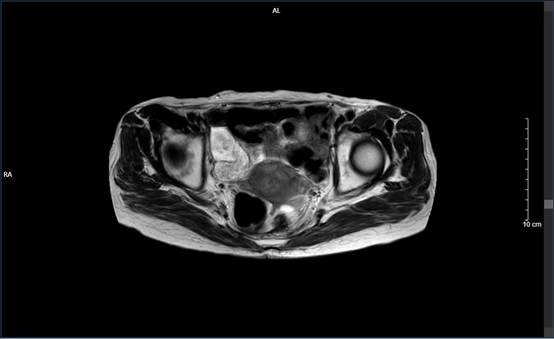

刘奶奶在家人的陪同下,从湛江赶往广州市从化区南医五院。王芝钧主任接诊后,经过相关完善检查后考虑盆腔占位、右下腹占位,考虑直肠癌复发、子宫恶性肿瘤可能。

完善相关检查后立即启动多学科MDT会诊,决定行腹腔镜探查术。由于既往腹腔手术史,再次手术难度高,王芝钧主任团队联合妇科刘芳主任团队,共同为刘奶奶开展腹腔镜手术。